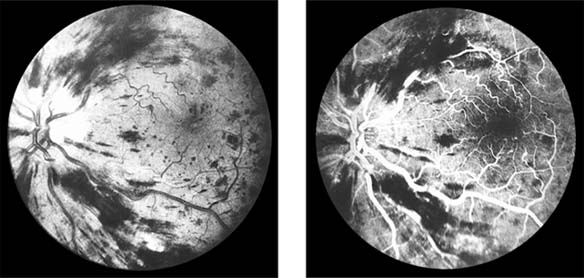

Figure 15-7

Figure 15-7: Central retinal vein occlusion. Left: Photograph shows linear hemorrhages in the nerve fiber layer and punctate hemorrhages in the deeper retinal layers. Right: Fluorescein angiogram shows dilation of the veins.

Fundus examination shows dilated tortuous veins with retinal and macular edema, hemorrhages all over the posterior pole, and cotton-wool spots. The arterioles are usually attenuated, indicating generalized microvascular disease.

The prognosis for vision is poor. Fluorescein angiography demonstrates two types of response: a nonischemic type, with dilation of retinal vessels and edema; and an ischemic type, with large areas of capillary nonperfusion or evidence of retinal or anterior segment neovascularization. In 93% of ischemic and 50% of nonischemic central retinal vein occlusions, the ultimate visual acuity is less than 20/200.